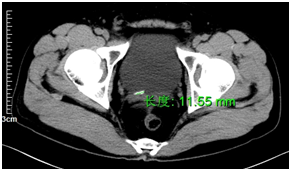

Ultrasonography of urinary system showed hydronephrosis of right kidney, calculus of right distal ureter and small perirenal effusion. Ultrasonography of digestive system showed no abnormality of liver, pancreas and spleen. There was no improvement, treated by a medical expulsive therapy for 2 days. A subsequent CTU (Computed Tomography Urography) scan showed right hydronephrosi and right lower ureteral stones 2-11 mm (Figure 1). A vast shadow of water with CT value about 2-10 HU is around the right kidney and upper ureter (Figure 2). The ureteral rupture with leakage of contrast is shown from the proximal ureter at the level of the 3rd lumbar vertebra.

Figure 1 Right lower ureteral stones 2-11 mm